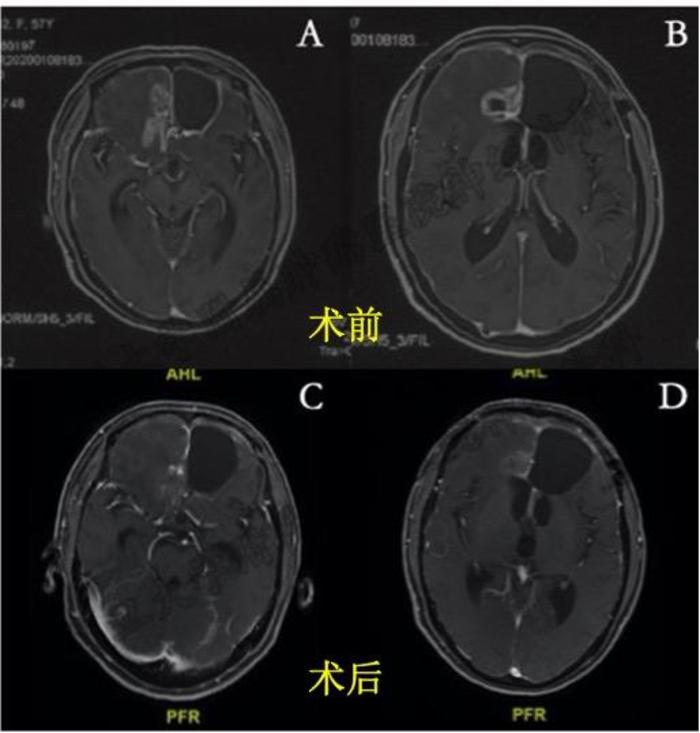

患者,女性,58岁,因左侧额叶及胼胝体胶质母细胞瘤术后复发1入院;20191119日,外院行左侧额叶肿瘤切除术,术后病理提示为胶质母细胞瘤,WHO Ⅳ级。术后采用诱导化疗(替莫唑胺(TMZ)75mg/m2/d+同步放化疗(TMZ75mg/m2/d+重离子15GyE/3Fx+质子60GyE/30Fx+辅助化疗(替莫唑胺150-200mg/m2/d10周期)方案治疗。202016日复查MRI提示右侧额叶及胼胝体胶质瘤复发(1.A B)

1.动脉介入治疗后肿瘤得到明显控制

术后2周复查头颅MRI提示胶质瘤范围及强化程度减轻。患者病情稳定,顺利出院。